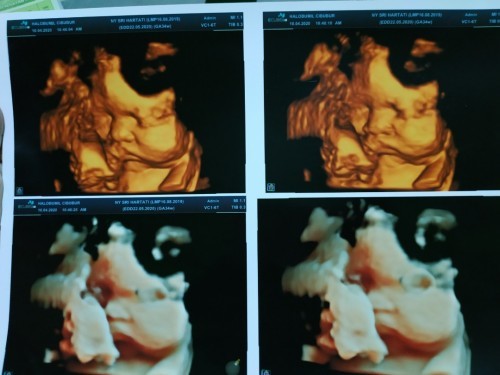

Nih Bun,. Pipinya menggemaskan sampe sekarang pun udah jalan 6 bulan 😊

Itu pas 28 week Bun.. dokternya jg gemes sama pipinya 😁